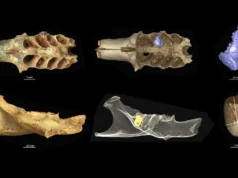

Para explorar o que muda nos pulmões mais velhos, os investigadores concentraram-se nos fibroblastos, células estruturais que ajudam a manter o tecido pulmonar. Em experiências com ratos jovens, activaram um sinal de stress normalmente associado ao envelhecimento. Isto levou à formação de aglomerados de células inflamatórias nos pulmões, algumas das quais foram identificadas pelo gene GZMK, que foi identificado pela primeira vez em casos graves de COVID-19. Os cientistas acreditam que tratamentos futuros poderão ter como alvo essas células para interromper o ciclo prejudicial conhecido como inflamação.

Eles examinaram uma via chamada NF-kB, que é comumente associada a doenças do envelhecimento. Quando ativados, os fibroblastos sinalizam aos macrófagos nos pulmões para iniciar uma resposta imune. Esta resposta atrai então células imunológicas adicionais da corrente sanguínea, incluindo aquelas marcadas por GZMK.

Embora estas células GZMK não fossem eficazes no combate à infecção, ainda eram capazes de danificar o tecido pulmonar.

Aglomerados de células imunológicas e danos pulmonares

Após a formação desses aglomerados de células imunológicas, os camundongos jovens desenvolvem sintomas graves quando infectados, semelhantes à resposta normalmente observada em adultos mais velhos. Quando os pesquisadores usaram um método genético para remover as células GZMK, os ratos conseguiram tolerar melhor a infecção.

Os pesquisadores também examinaram o tecido pulmonar de pacientes idosos hospitalizados com SDRA (síndrome do desconforto respiratório agudo) relacionada à Covid. Estas amostras continham aglomerados de células inflamatórias semelhantes às observadas em ratos. Pacientes mais gravemente doentes tiveram um número maior desses grupos, enquanto pulmões de doadores saudáveis não apresentaram nenhum.